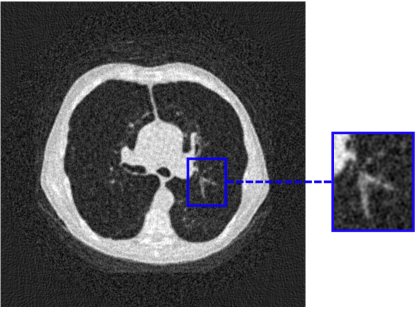

To assess the performance of the HLSF, four phantoms with structural patterns of different complexity have been considered (Fig. 4). PH-1 in Fig. 4(a) is the segmentation of a reconstructed slice of mouse lung tissue at micrometer scale. PH-2 in Fig. 4(b) is a multilevel segmentation of a MRI scan of a human brain. PH-3 in Fig. 4(c) is a multilevel segmentation of a CT slice of a human lung. PH-4 is the well-known Shepp-Logan phantom [16].

Refer to caption

(a) PH-1

(b) PH-2

(c) PH-3

(d) PH-4

Figure 4: Set of simulated data used to benchmark the HLSF. PH-1 has 784 ×\times 784 pixels; PH-2 has 592 ×\times 592 pixels; PH-3 has 500 ×\times 500 pixels; PH-4 has 512 ×\times 512 pixels.